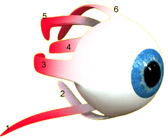

Rectus medialis

De beweging van ogen wordt verzorgd door heel kleine sp...

Onderste schuine oogspier

De beweging van de oogballen wordt bestuurd door kleine...

Bovenste rechte oogspier

De beweging van de oogballen wordt bestuurd door kleine...